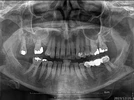

Diş hekimi